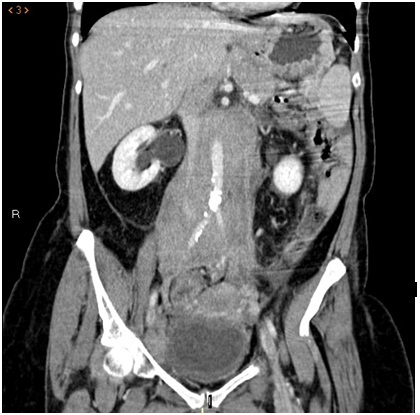

Abdominal CT: a large retroperitoneal mass is observed that involves vascular structures with thickening and hypercaptation of rectum, cecum and terminal ileum walls, as well as multiple inguinal adenopathies, the largest in the left iliac fossa of 26mm.

Figure 1 Sagital Scanner Tomography. Aortoiliac lymphadenopathies.

Figure 2 Axial Scanner Tomography. Retroperitoneal lymph nodes.

Figure 3 Coronal scanner. Polyadenopathic process involving vascular structures.